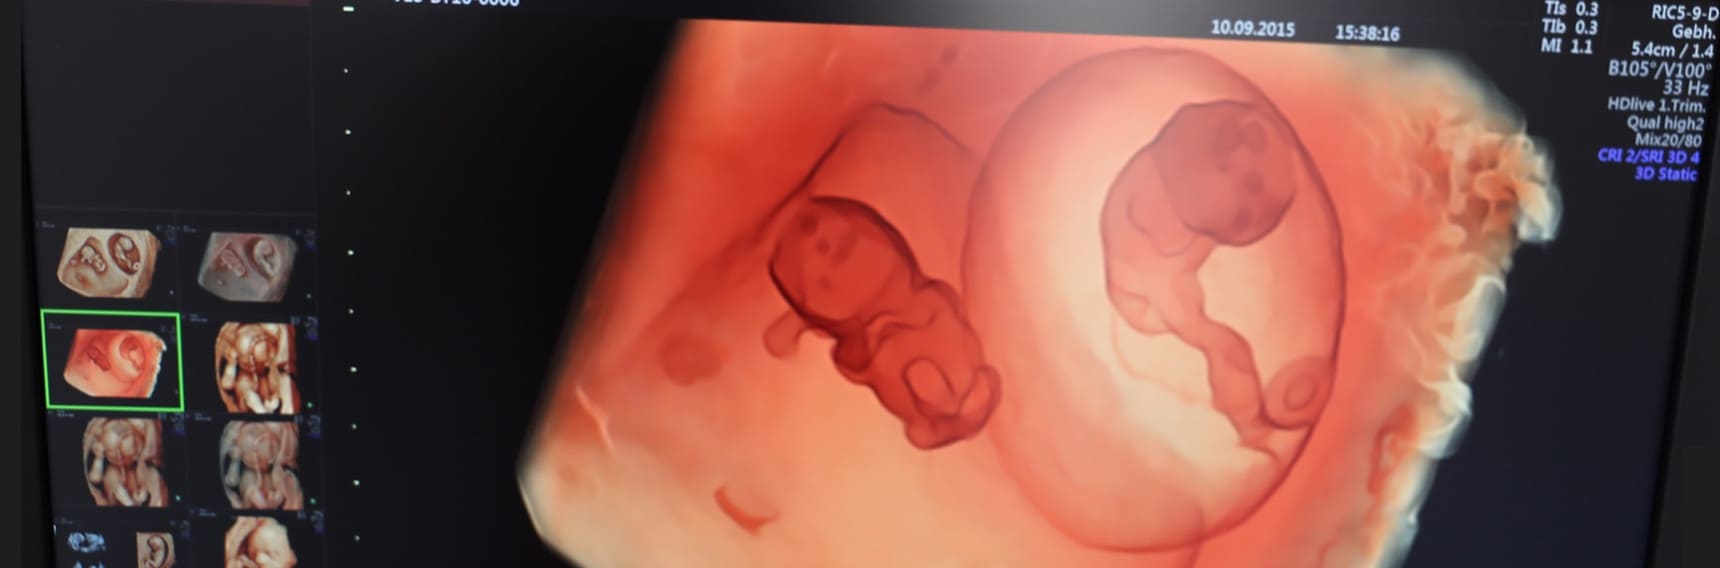

Ecografía 5D HD Live Más información